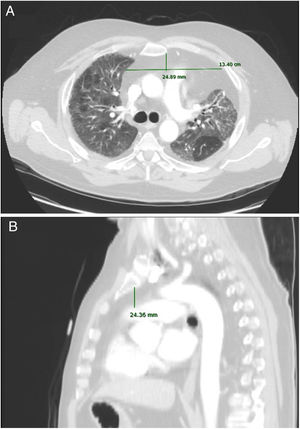

Anteroposterior axis (AP): from the posterior wall of sternum to the anterior wall of pulmonary artery, measured in the CT-axial plane (Fig. 2).

Transverse axis (T): distance between both mediastinal pleurae, obtained at the same level of AP axis, and measured in the CT-axial plane (Fig. 2).

Height (H): from posterior wall of the sternal notch to the main pulmonary artery trunk, measured in the sagittal plane (Fig. 2).

AMF volumes (V) were calculated by using the formula: AP×T×H×3.14/6, following a similar method to calculate prostatic volumes.10